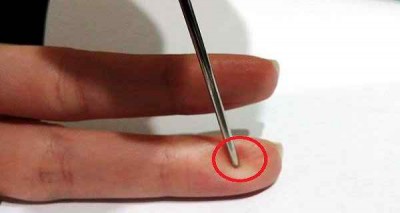

চীনে সুঁই দিয়ে ব্রেইন স্টোক প্রতিরোধ

চীনের অধ্যাপকরা বলছেন যে কারো স্ট্রোক হচ্ছে যদি এমন দেখেন তাহলে আপনাকে নিম্নলিখিত পদ্ধতি অবলম্বন করতে হবে: যখন কেউ স্ট্রোকে ..বিস্তারিত